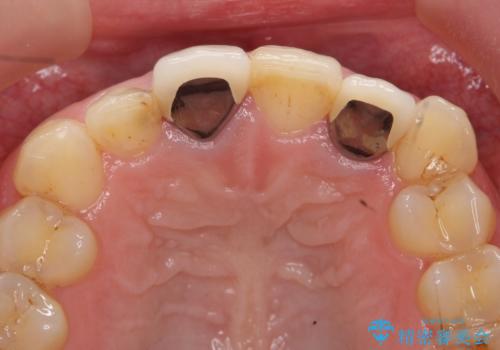

- 前歯の色や長さ、歯茎との隙間の金属が気になるのでセラミックで治療したいといらっしゃった方の症例です。

見た目改善のため、前歯4本をオールセラミッククラウン(スペシャル)で補綴しました。

右上1と左上2は再根管治療を行っております。